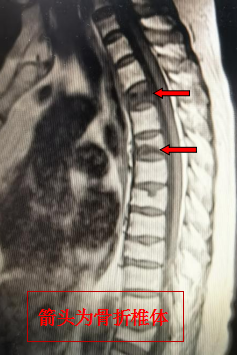

此次接受手术的患者为65岁女性,因胸背部疼痛1个月急诊入住呼吸与危重症医学科,当时病情比较严重,经治疗后患者肺部情况得以控制,但仍感胸背部疼痛,转脊柱外科会诊,脊柱外科主任况光荣认真仔细为患者检查后,考虑其长期应用激素治疗哮喘,同时合并骨质疏松,加上近日哮喘发作、肺部情况加重,频繁咳嗽引起椎体脆性骨折。待患者肺部情况相对稳定后,由呼吸与危重症医学科转入脊柱外科,完善骨密度检查后确诊为重度骨质疏松(骨质疏松症(osteoporosis, OP)是最常见的骨骼疾病, 是一种以骨量低,骨组织微结构损坏,导致骨脆性增加,易发生骨折为特征的全身性骨病)。核磁检查发现第3、5胸椎椎体压缩骨折。

通过详细分析讨论,考虑患者脊柱后凸畸形、胸廓活动受限,呼吸受限,加上合并肺部感染,长期疼痛睡眠质量差,胸椎骨折与肺部感染恶性循环,疼痛不缓解,痰液难排出,肺部感染难好转。与患者及其家属沟通后拟采用创伤较小的“经皮椎体成形术” 手术治疗。